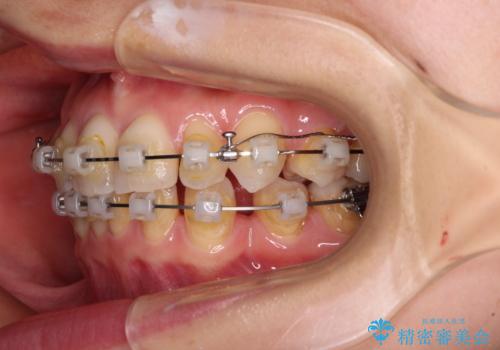

- クリアブラケット

- 3年8ヶ月

- 30回以上

アンカースクリューを用いて正中位置を調整したことで、上下の正中位置をほぼ一致させることができました。

移動量が多かったため、治療期間は長くなりましたが、大変満足のいく仕上がりとなりました。